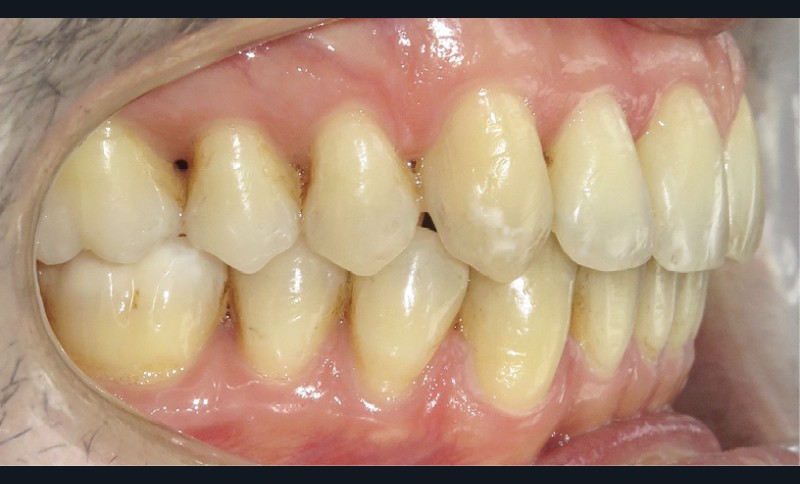

Une fois le sens transversal traité, la correction s’est portée sur le décalage sagittal de Classe II au niveau dentaire (fig. 3). La présence de tip forward sur les dents des secteurs latéraux maxillaires signifie que les apex de ces dents sont plus ou moins bien placés. Des mouvements de version sont suffisants. C’est pourquoi a été retenue la solution suivante :

- collage au maxillaire d’un segment d’arc acier 019 x 025 (traité au rhodium à des fins esthétiques) sur les canines et les premières molaires maxillaires avec du composite (contenu dans une carpule) destiné au collage des fils contention (choisi pour sa résistance et sa facilité de mise en œuvre) ;

- réalisation d’une gouttière mandibulaire rigide englobant l’ensemble des dents mandibulaires. Cette gouttière a pour but de relier l’ensemble des dents de l’arcade inférieure (ancrage) et d’obtenir une désocclusion.

- collage de boutons sur les 13 et 23 (en composite pour améliorer l’esthétique) et de boutons métalliques (pour le confort) sur les 36 46

- port d’élastiques (3/16 4,5 Oz) reliant les boutons maxillaires à ceux mandibulaires pour obtenir une force de recul sur l’arcade supérieure et d’avancée sur l’arcade opposée (les mouvements ont été facilités par les extractions des 18 28). Les prémolaires n’étant pas collées, le mouvement généré est un mouvement de version et donc de redressement (car tipées au départ). Il est à noter que les boutons canins sont collés le plus cervicalement possible pour avoir une traction oblique avec les élastiques inter-arcades, afin d’avoir un mouvement de descente des canines supérieures qui sont trop hautes. L’intérêt d’avoir une gouttière mandibulaire par rapport à un arc lingual ou un dispositif multi-attaches, c’est qu’une gouttière contrôle mieux les mouvements de vestibulo-version des incisives mandibulaires induits par les élastiques.